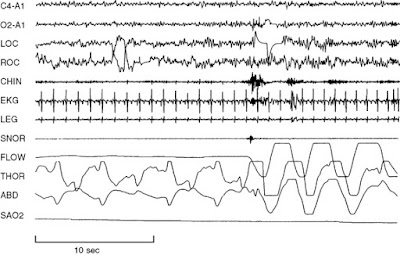

Najczęściej stosowanym testem w diagnostyce zespołu obturacyjnego bezdechu sennego (OBS) jest nocna polisomnografia laboratoryjna (PSG). Jest ona zalecana jako podstawowe kryterium rozpoznawania OBS, określania nasilenia choroby i oceny różnych innych zaburzeń snu, które mogą występować wspólnie z OBS albo niezależnie od niego. PSG polega na jednoczesnym rejestrowaniu wielu parametrów fizjologicznych związanych ze snem i czuwaniem. . Domowe, ograniczone pod względem ilości rejestrowanych kanałów, badania snu są częściej wykorzystywane do przesiewowego wykrywania i wstępnego diagnozowania obturacyjnego bezdechu sennego.

PSG może bezpośrednio monitorować i kwantyfikować liczbę epizodów oddechowych (tj. obturacyjnych, centralnych lub złożonych) oraz wynikającą z nich niedotlenienie i wybudzenia związane z wydarzeniami oddechowymi lub nawet niezależne od zdarzeń oddechowych. Jednonocne PSG jest zazwyczaj wystarczające do potwierdzenia diagnozy bezdechu sennego i jaki jest stopień zaburzenia.

Ocena etapów snu wymaga 3 badań:- elektroencefalografii (EEG) - aktywność elektryczna mózgu

- elektrookulografii (EOG) - ruchy gałek ocznych

- elektromiografii powierzchniowej (EMG) - aktywność mięśniowa

Jeden kanał EEG (centralny z odniesieniem do słuchu) jest używany do monitorowania etapu snu. Jednak większość laboratoriów korzysta z 2 kanałów centralnych i 2 kanałów potylicznych, a odniesienia do kanału z odniesieniem do słuchu są pomocne w identyfikacji opóźnienia snu i wybudzeń. W celu określenia lokalizacji tych kanałów stosuje się system rozmieszczenia 10-20 elektrod. Dodatkowe kanały EEG mogą być wykorzystywane, szczególnie u pacjentów z padaczką.

Dwa kanały EOG są wykorzystywane do monitorowania zarówno poziomych, jak i pionowych ruchów oczu. Elektrody umieszczone są po prawej i lewej stronie, jedna powyżej i jedna poniżej poziomej osi oka. Ocena ruchów gałek ocznych jest konieczna z 2 powodów. Pierwszym z nich jest dokumentowanie początku fazy szybkich ruchów gałek ocznych (REM), a drugim jest odnotowanie obecności wolnoobrotowych ruchów gałek ocznych, które zazwyczaj towarzyszą początkowi snu.

Jeden kanał EMG (zazwyczaj podbródek) jest używany do rejestrowania atonii mięśniowej podczas snu REM lub braku atonii u pacjentów z parazynomniami związanymi z REM. Aby ocenić bruksizm, elektrody EMG można umieścić także nad żwaczem. Rejestracja EMG z innych grup mięśni jest oceniana pod kątem innych zaburzeń snu. Na przykład EMG kości piszczelowej przedniej jest pomocne w ocenie okresowych ruchów kończyn podczas snu, a EMG międzyżebrowe jest wykorzystywane jako pomoc w określaniu wysiłku podczas zdarzeń związanych z oddychaniem.

Dwa kolejne kanały służą do monitorowania przepływu powietrza. Jeden kanał termistorowy (ustny i/lub nosowy) służy do oceny obecności lub braku przepływu powietrza. Każda zmiana temperatury w miarę jak pacjent wdycha i wydycha prowadzi do powstania sygnału, więc ten kanał jest niewrażliwy na tylko częściową blokadę przepływu. Termistor jest zalecanym kanałem do oceny bezdechu. Kanał przetwornika ciśnienia w nosie jest bardziej czułą miarą ograniczenia przepływu powietrza. Normalne oddychanie ma zaokrąglony wzór, podczas gdy opór przepływu powietrza prowadzi do wyrównania sygnału przepływu. Przetwornik ciśnienia jest zalecanym kanałem do oceny spłyceń oddechu. Jest on również stosowany do oporu przepływu powietrza w zespole oporu górnych dróg oddechowych.Inne parametry, które mogą być monitorowane w badaniu snu, obejmują następujące elementy:

- Elektrokardiografia

- Oksymetria impulsowa

- Wysiłek oddechowy (piersiowy i brzuszny)